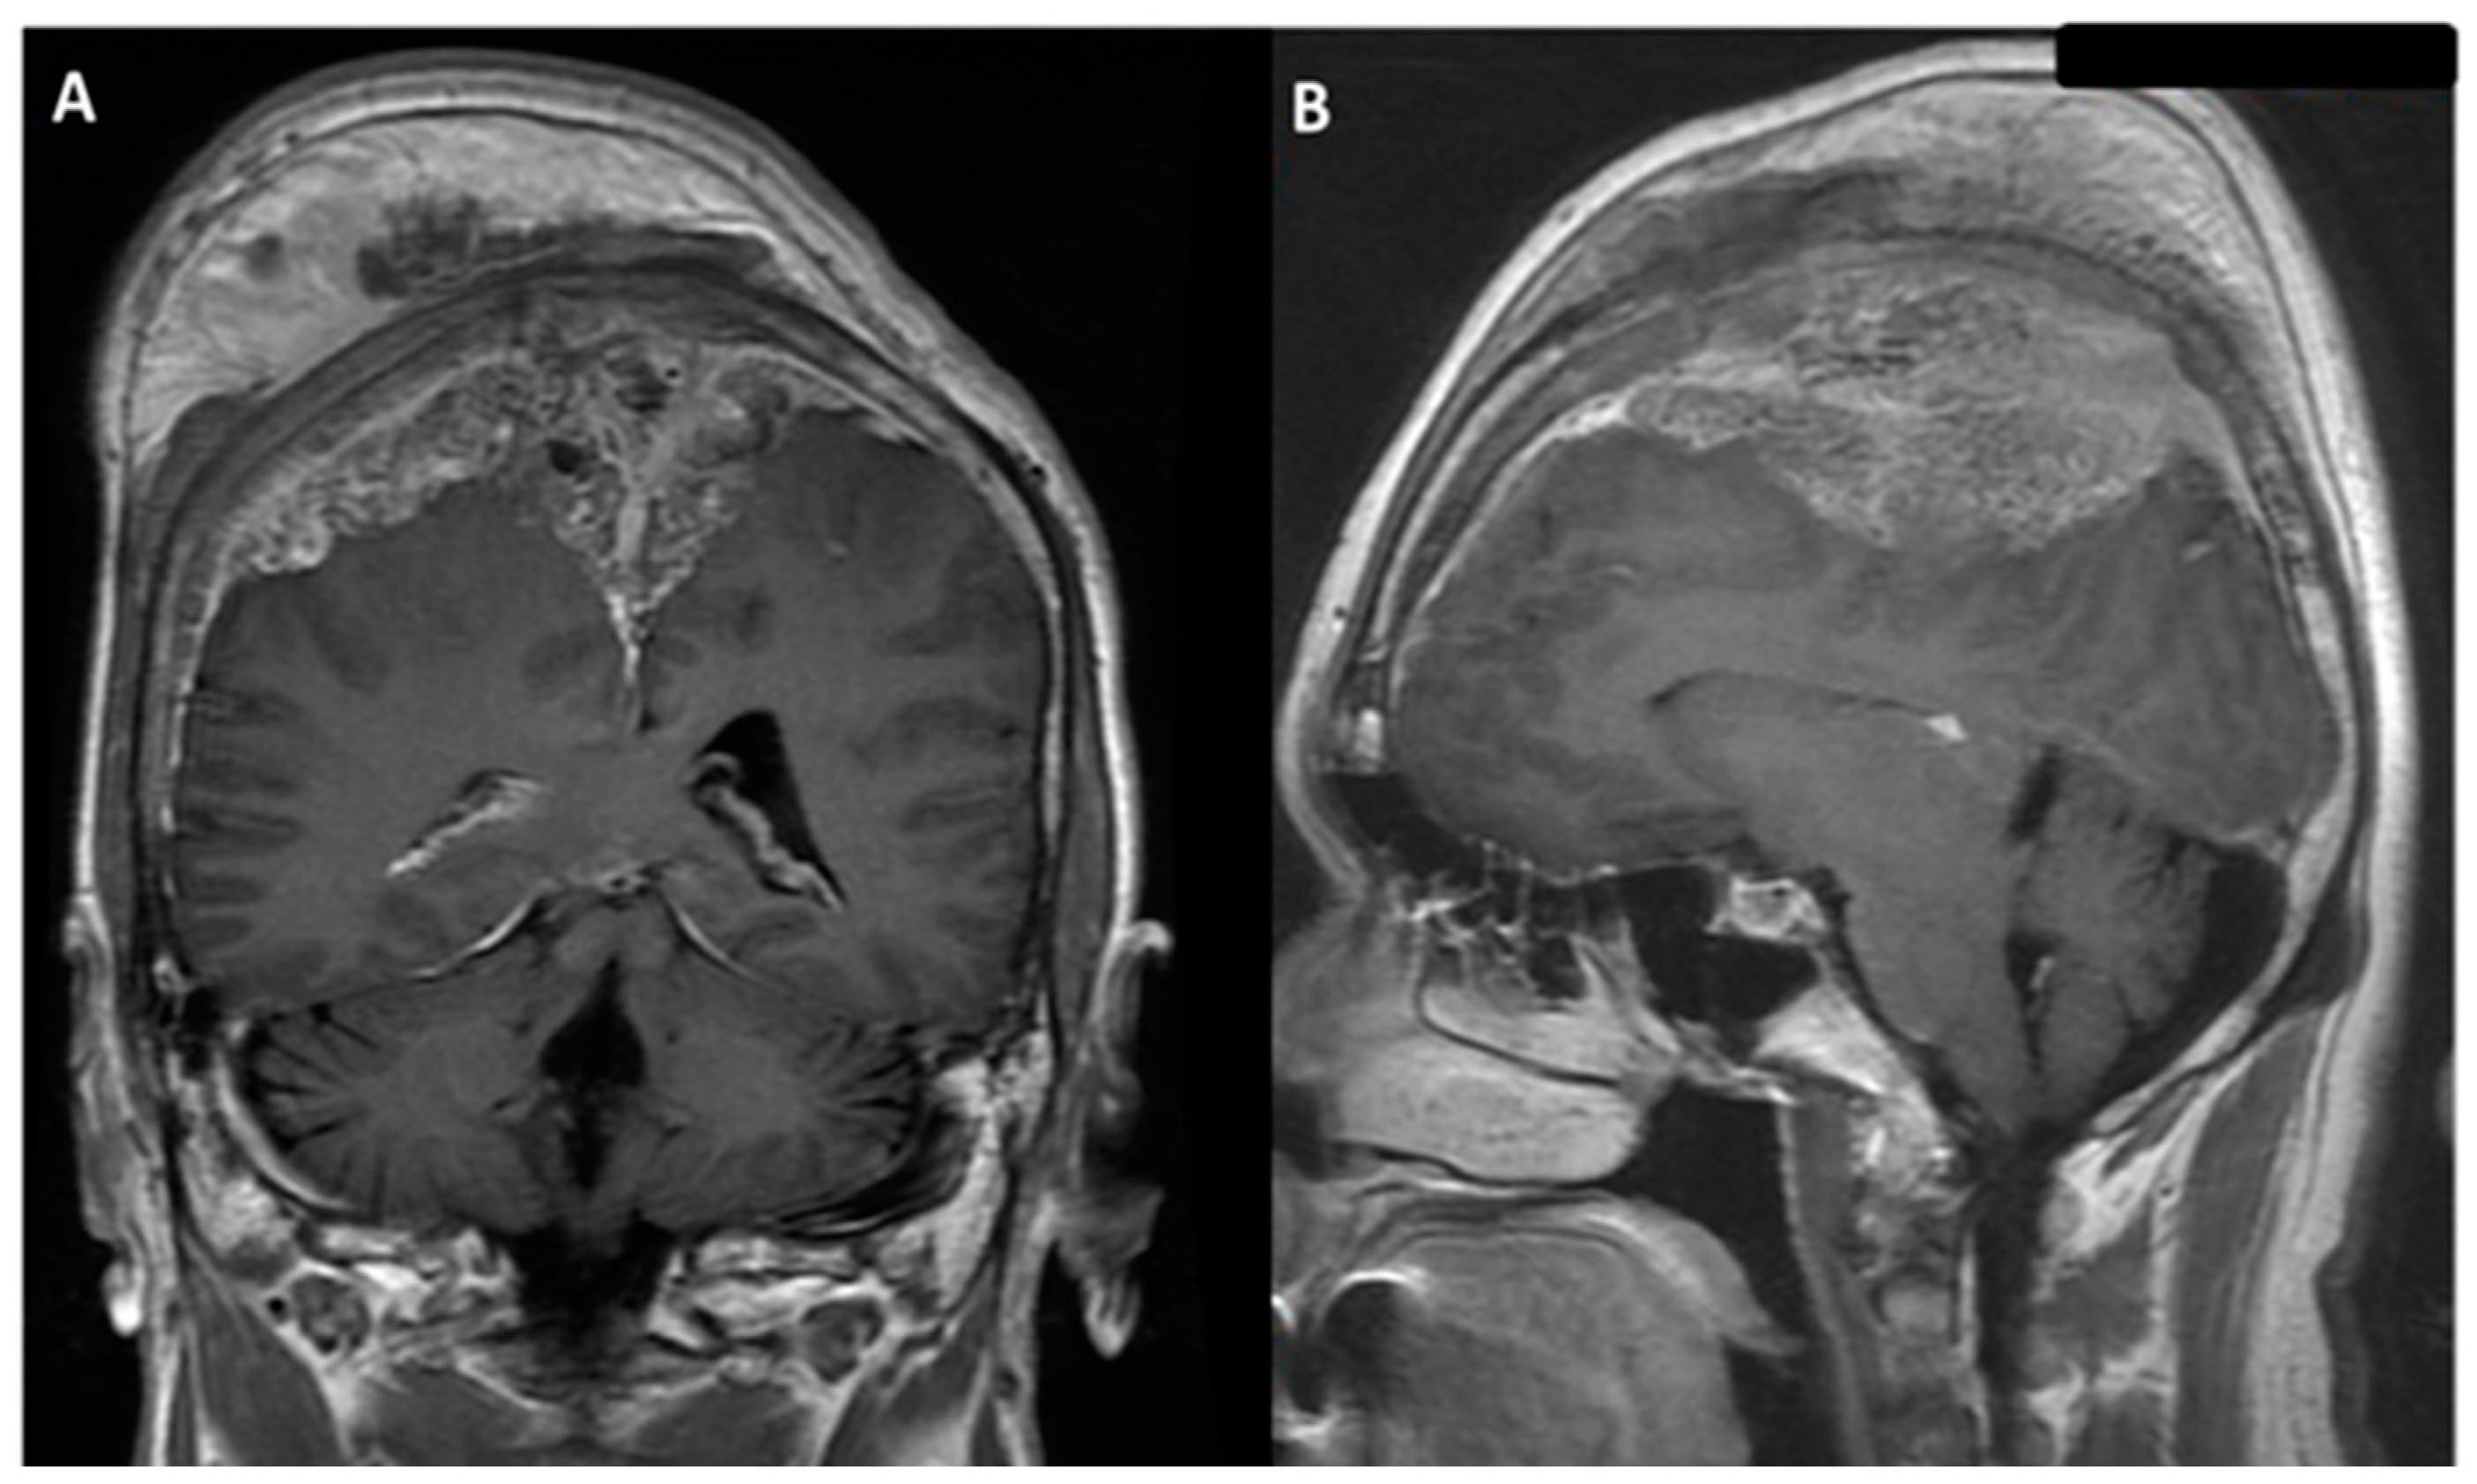

2.1. Our Case Description

| Tsai et al., 2021 | 55/M | Seizure, loss of consciousness | 91 | bilateral | occluded | II | I | 2/5 left arm and left leg 0/5 right leg | Preserved | Aphasia | Aphasia recovery within 7 days; muscle power recovery within 7 weeks |